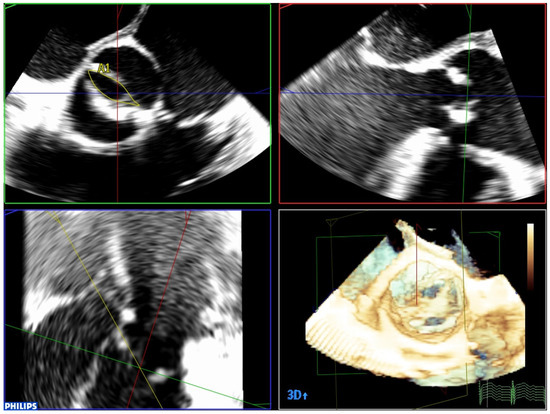

| 3 | Three-dimensional TEE is the best technique to detect and quantify perivalvular regurgitation after TAVR implantation, a fundamental aspect in deciding whether immediate valve postdilation is needed or not. |

| 5 | Three-dimensional TEE allows us to accurately evaluate cardiac function after TAVR, with important aspects such as systolic function or mitral valve function, which can be affected by TAVR when the implant is low, or due to damage caused to the subvalvular apparatus by the catheters and guides. |